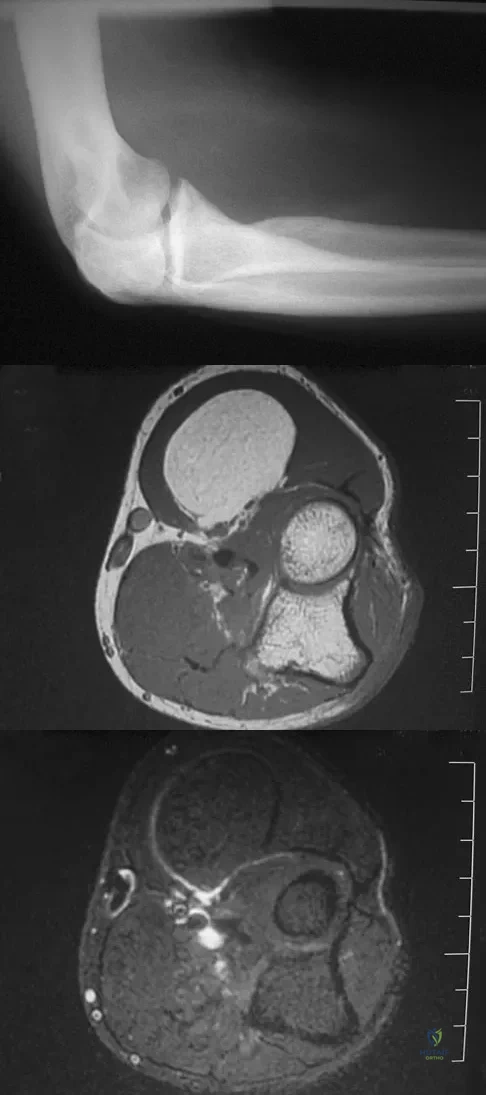

Question 24

A 33-year-old man reports an enlarging painful soft-tissue mass in his right forearm. A radiograph and MRI scans are shown in Figures 45a through 45c. Treatment should consist of

Explanation